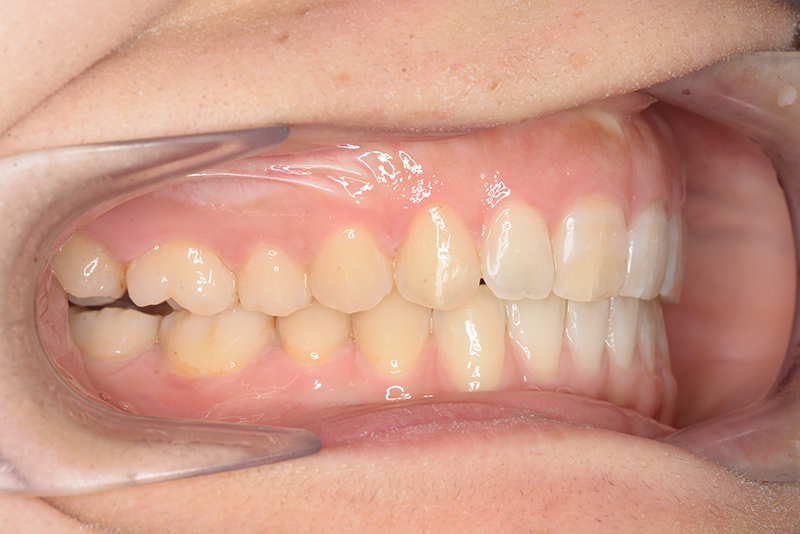

初診時

FP・IOP

口腔内所見 大臼歯、犬歯関係はⅡ級で、上顎中切歯は舌側傾斜しており、over jet1.5mm,over bite 6.0mmいわゆるⅡ級2類であった。